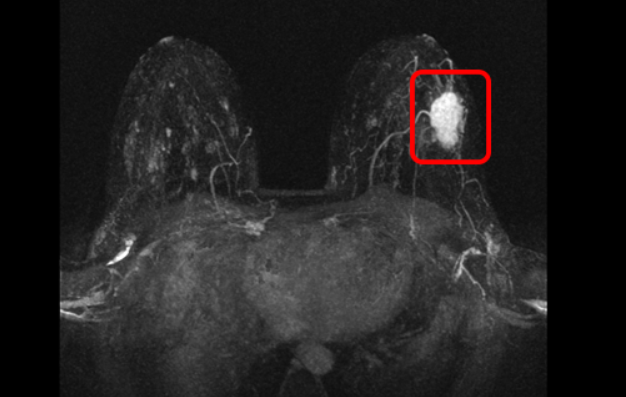

- ошибочная интерпретация результатов маммографии, ультразвуковой диагностики и МРТ молочных желез;

Фиброаденома – это самая распространенная доброкачественная опухоль молочной железы. Она имеет достаточно отличий от злокачественной опухоли. У фиброаденомы четкие и ровные контуры, горизонтальная пространственная ориентация, меньшая плотность в сравнении с раком. Однако, злокачественные опухоли небольших размеров могут имитировать фиброаденому.